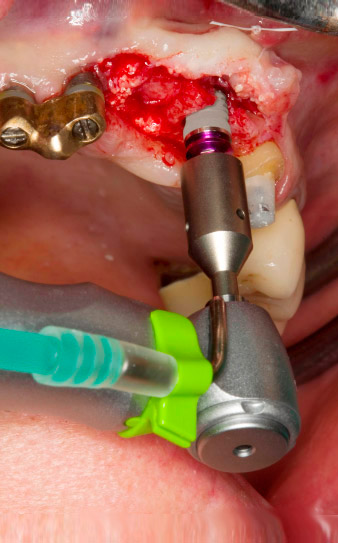

Sección de la rosca con el contra-ángulo WS-75 L

Imagen. 3: Sección de la rosca con el contra-ángulo WS-75 L con una transmisión de 20:1 (programa P4). En este caso, resultan útiles el alto torque del Implantmed, el sistema de sujeción hexagonal para una transmisión segura de la fuerza y la inversión automática del sentido de giro cuando hay una alta resistencia.